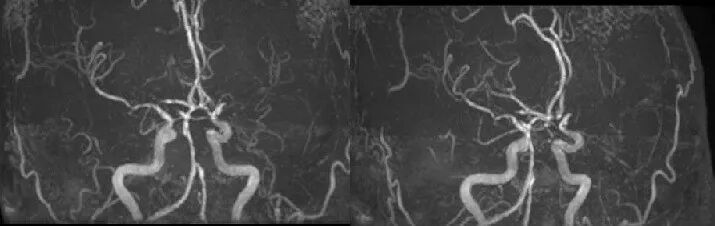

入院影像检查

导丝怎么扩【载药时代 球扩天下】NOVA DES®颅内药物洗脱支架在颅内富穿支区域使用体会二例!_https://www.jmylbn.com_新闻资讯_第10张

MRA

导丝怎么扩【载药时代 球扩天下】NOVA DES®颅内药物洗脱支架在颅内富穿支区域使用体会二例!_https://www.jmylbn.com_新闻资讯_第11张

DWI

重要影像结论:左侧额顶叶梗死灶(急性或亚急性期),较3月前明显增大,左侧大脑中动脉闭塞。